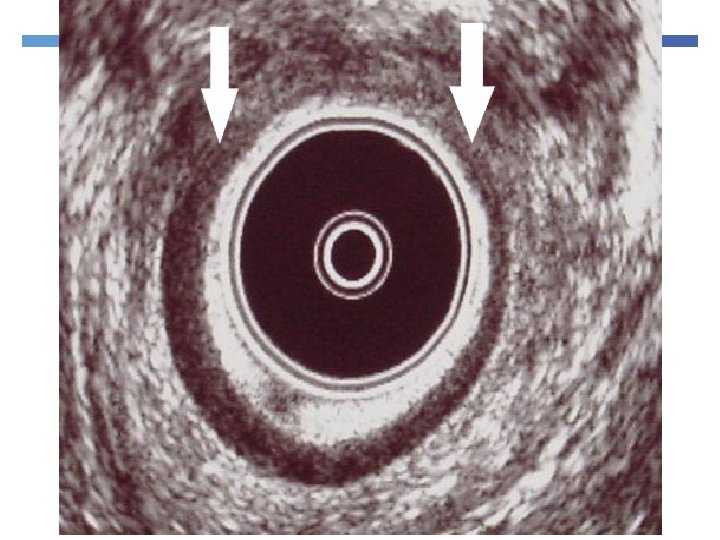

Endoanal Ultrasonography 360 degree rotating probe Simple and relatively painless Excellent visualization of the 5 layers of the anal canal

Endoanal Ultrasonography Muscle thickness Scarring Loss of muscle tissue

Endoanal Ultrasonography